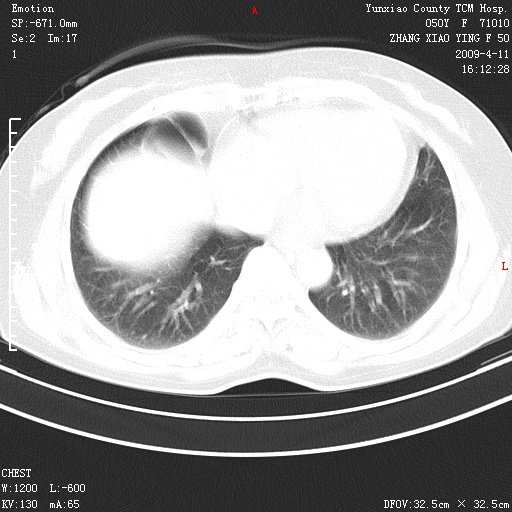

标题: CT19324:胸闷1周伴咳嗽 [打印本页]

标题: CT19324:胸闷1周伴咳嗽

病灶周围肺纹受压移位走行较柔和,余肺里实质均匀,纹理如常,肺间质无显著纤维化,支持考虑孤立性肺囊肿

考虑右肺中叶肺囊肿。